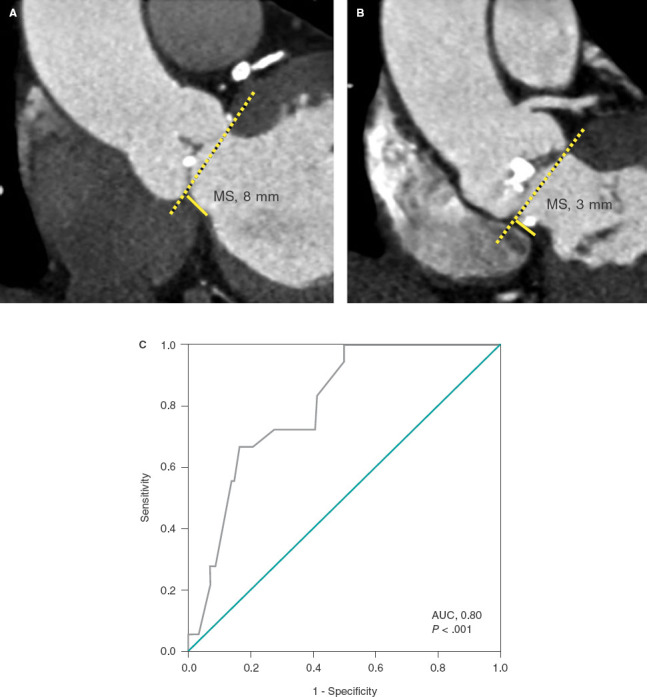

[Relationship between membranous septum length and need for pacemaker implantation after transcatheter aortic valve implantation].